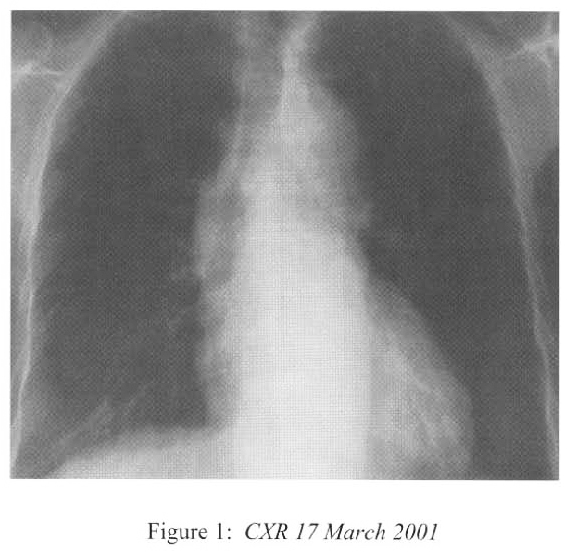

She was admitted to the medical ward on 17th March 2001 complaining of exertional dyspnoea, fever, chills and rigor. CXR showed right lower zone patch of consolidation (Figure 1) while baseline CXR in January 2001 was normal. She was treated with 1 week’s course of Ceftazidime. Steroid was continued while the cyclophosphamide was stopped. Fever resolved and the chest symptoms improved. However there was further deterioration of renal function in the next 10 days(creatinine 333–;>693 umol/L; creatinine clearance 8ml/minute). The clinical impression was progression to cresentic glomerulonephritis and she soon developed anuria before renal biopsy could be repeated and required peritoneal dialysis.